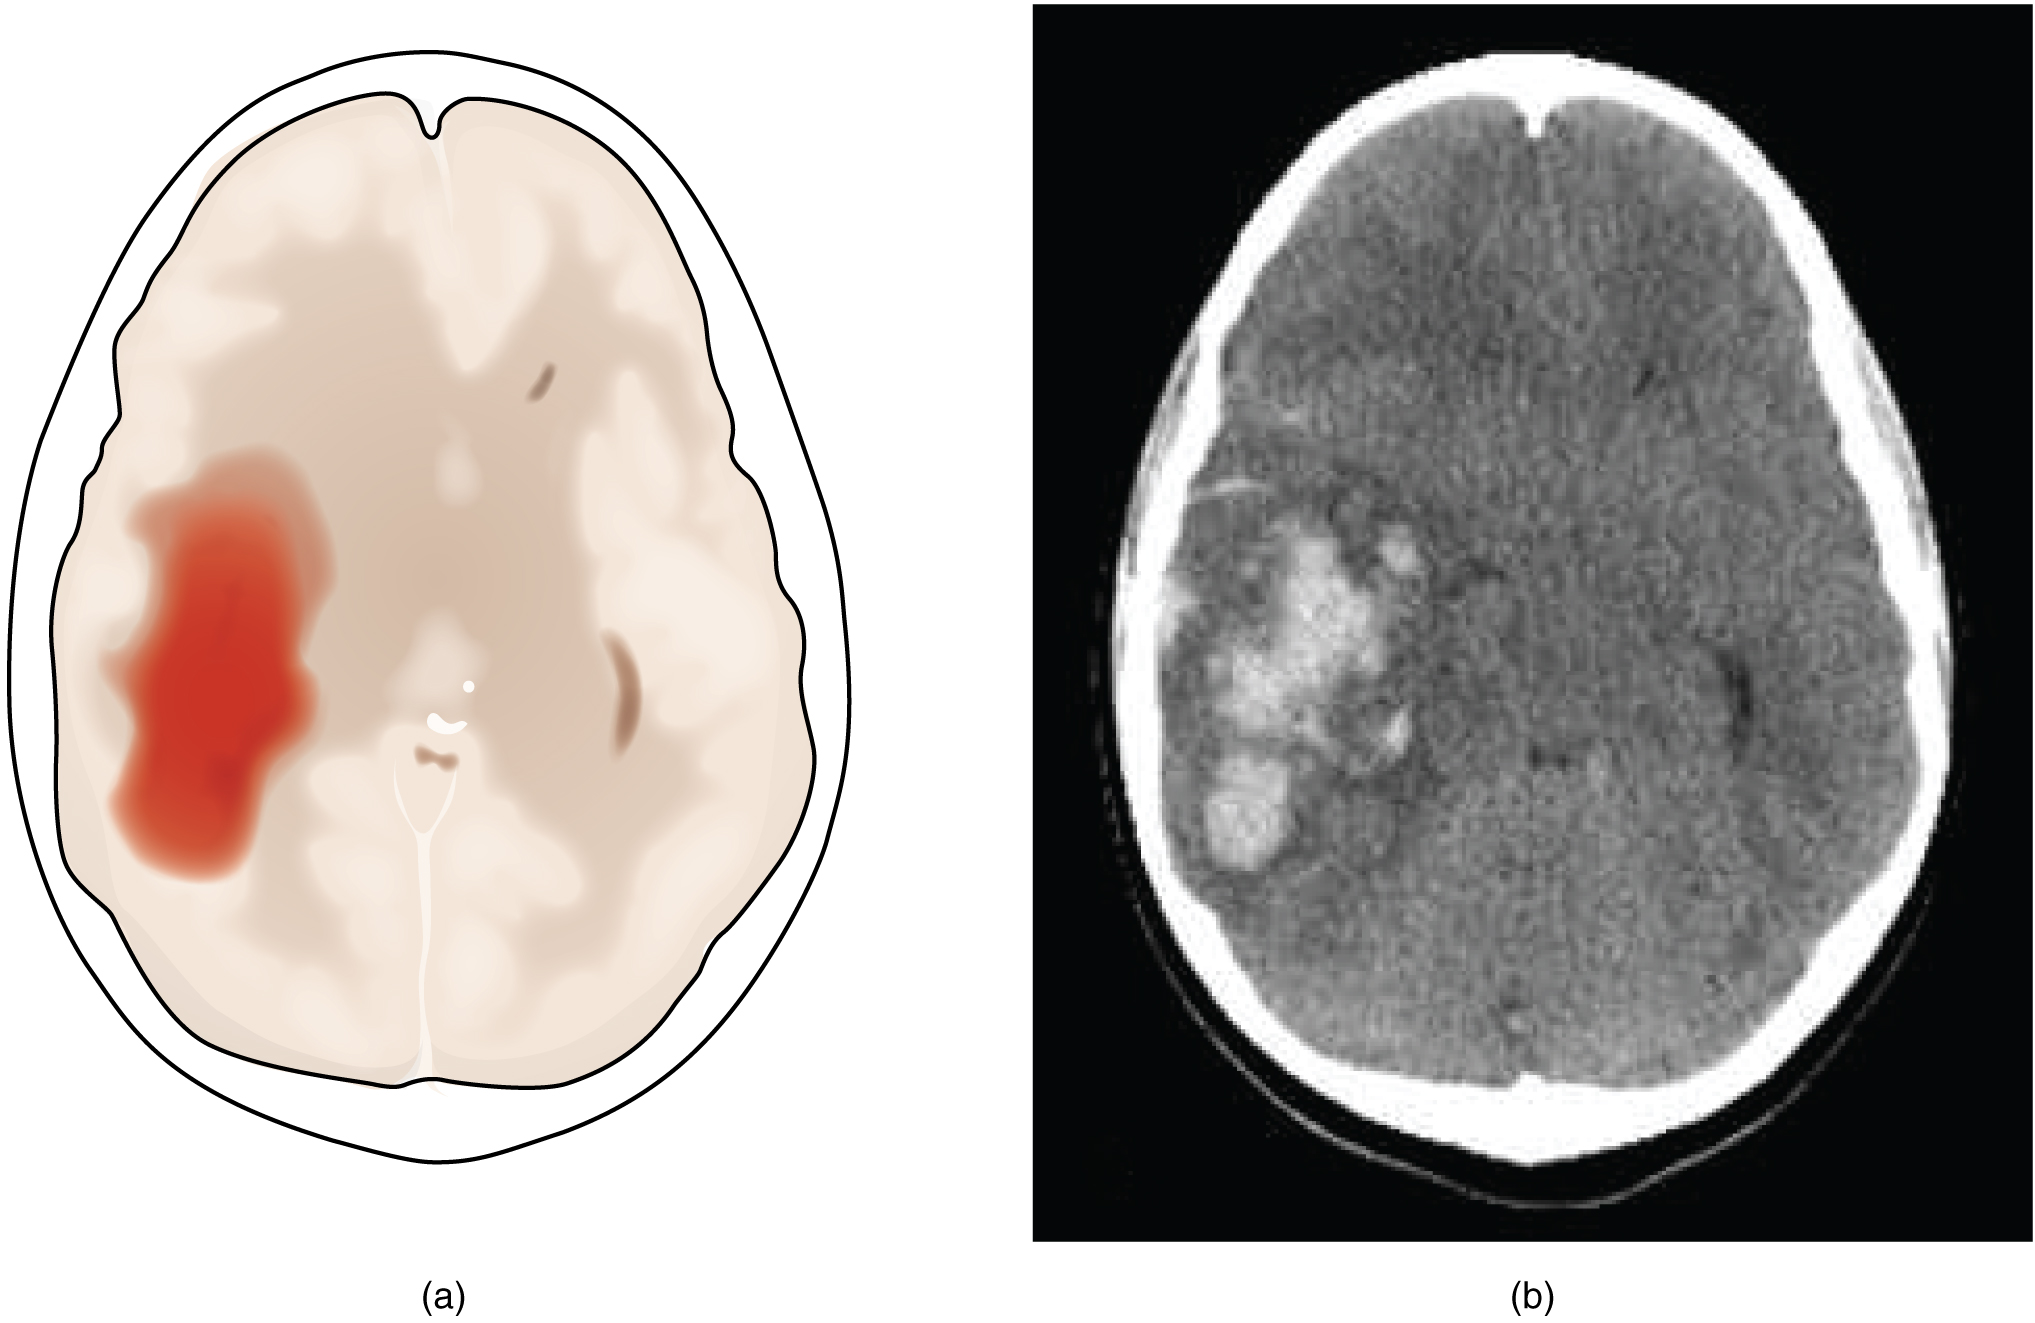

A hemorrhagic stroke is bleeding into the brain because of a damaged blood vessel. Accumulated blood fills a region of the cranial vault and presses against the tissue in the brain ([link]). Physical pressure on the brain can cause the loss of function, as well as the squeezing of local arteries resulting in compromised blood flow beyond the site of the hemorrhage. As blood pools in the nervous tissue and the vasculature is damaged, the blood-brain barrier can break down and allow additional fluid to accumulate in the region, which is known as edema.